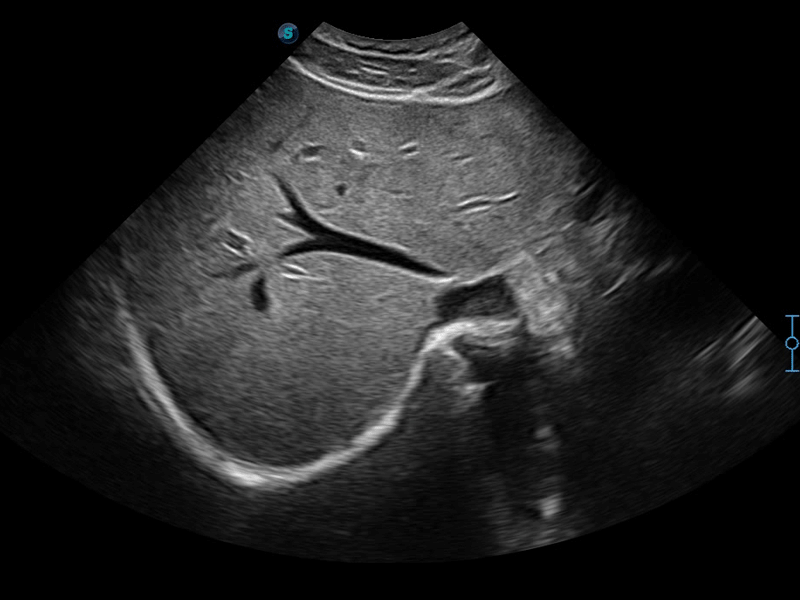

造影成像

造影成像功能和定量分析工具包使医生能够更好的评估血流灌注情况。独特的动态声压控技术有效控制造影剂的声压,保证更长的造影剂持续时间,更好的观察病变灌注的延迟相位。